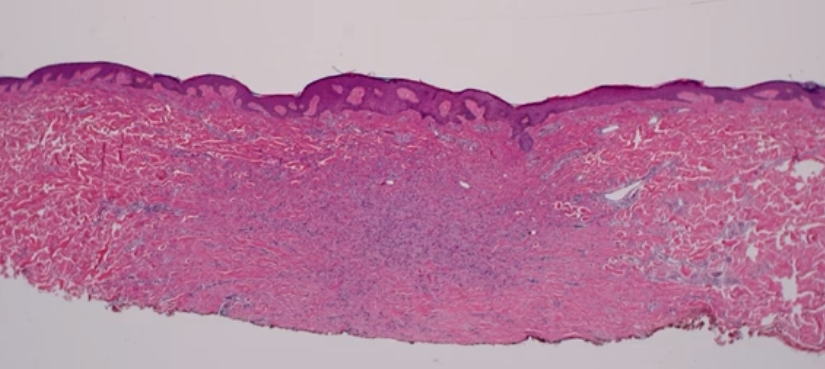

Dx

A

Angiofibroma

Histology of an angiofibroma

Dome shaped lesions with dermal proliferation of plump or stellate fibroblasts in a collagenous stroma with an increase in the number of thin-walled, dilated blood vessels

Histology of a dermatofibroma

Induction of the epidermis - “tabling”

Spindle cell proliferation in the dermis

- haphazard

- jaggered edges (not smooth borders)

- entraps collagen bundles at the periphery

Can have haemosiderin staing, can have foamy or vacuolated appearance (xanthomatous) cytoplasm